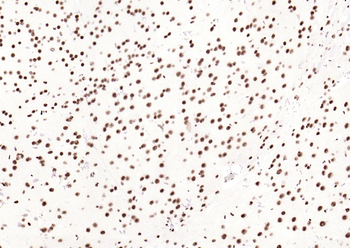

Phospho-Smad3 (Ser423 + Ser425) Rabbit Polyclonal Antibody [orb6983]

FC, IF, IHC-Fr, IHC-P, WB

Bovine, Canine, Equine, Gallus

Human, Mouse, Porcine, Rat

Rabbit

Polyclonal

Unconjugated

100 μl, 200 μl, 50 μlPhospho-SMAD5 (Ser463 + Ser465) Recombinant Rabbit Monoclonal Antibody [orb559123]